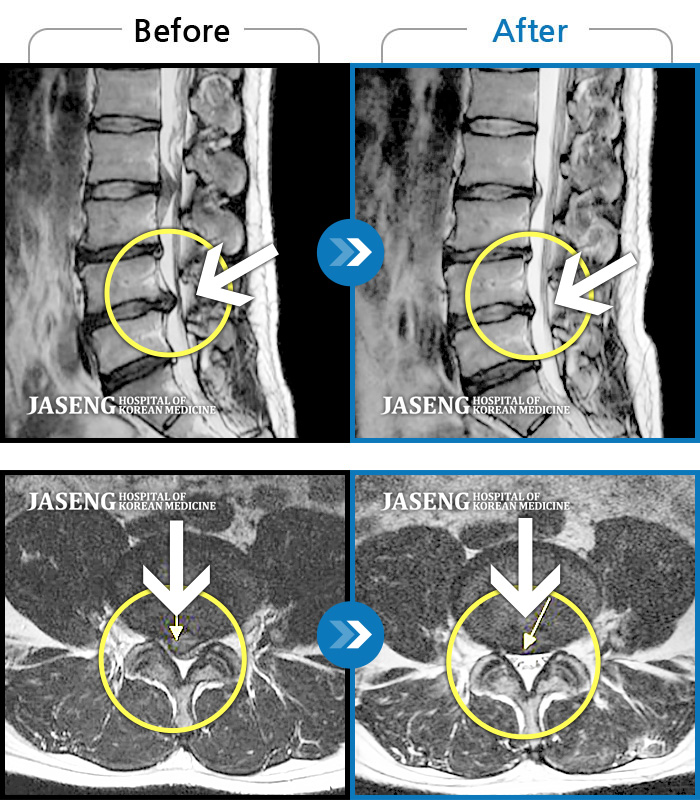

Before

After

환자에게 사전 동의를 받아 동일 조건에서 촬영되었습니다.

개인에 따라 치료 후 부작용이 발생할 수 있으니 의료진과 상담 후 치료를 진행하시기 바랍니다.

허리디스크로 우측 발목까지 방사통